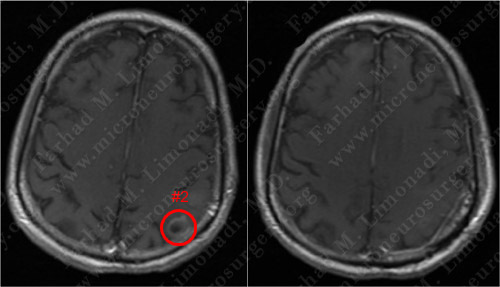

Before Operation Afer Operation

Post-op MRI shows radiographic resection of the first tumor.

Before Operation After Operation

Post-op MRI shows radiographic resection of the second tumor as well.